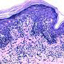

A rare case of scrofuloderma along with lupus vulgaris

Successfully maintained complete remission of mycosis fungoides by umbilical cord blood transplantation: a case report and literature review